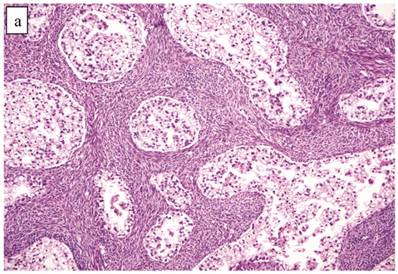

The clinicopathologic features with respect to age, stage, bilaterality, tumor size, and gross appearance are shown in Table 1. Histologically, the tumors contained a background of AF and exhibited greater glandular crowding as well as more variation in size and shape of glands, including cystic dilatation, compared with AFs (Fig. 2A). Occasional glands showed slightly more stratification of the epithelium (2-4 layers) but generally did not have substantial architectural complexity, such as papillary, solid, or cribriform patterns. The nuclei were mostly small, uniform, and flat to round but occasionally had mild nuclear enlargement and slight hyperchromasia; nucleoli, if present, were usually small (Fig. 2B).

Atypical proliferative (borderline) clear cell tumor. (A) The glands show a greater degree of crowding and variation in size and shape compared with clear cell adenofibroma. (B) The glands in many areas are lined by flat non-atypical cells. (C) Focal notable nuclear atypia is present in the glandular epithelium.

Only one case had mitotic activity (1 MF/10 HPFs). Notable nuclear atypia was focally present in 11 (27%) cases (Fig. 2C); however, such foci lacked associated stromal alterations and recognizable forms of invasion, such as an haphazard infiltration of glands, glandular confluence, mitotic activity within glands, or the conventional appearance of clear cell CA.